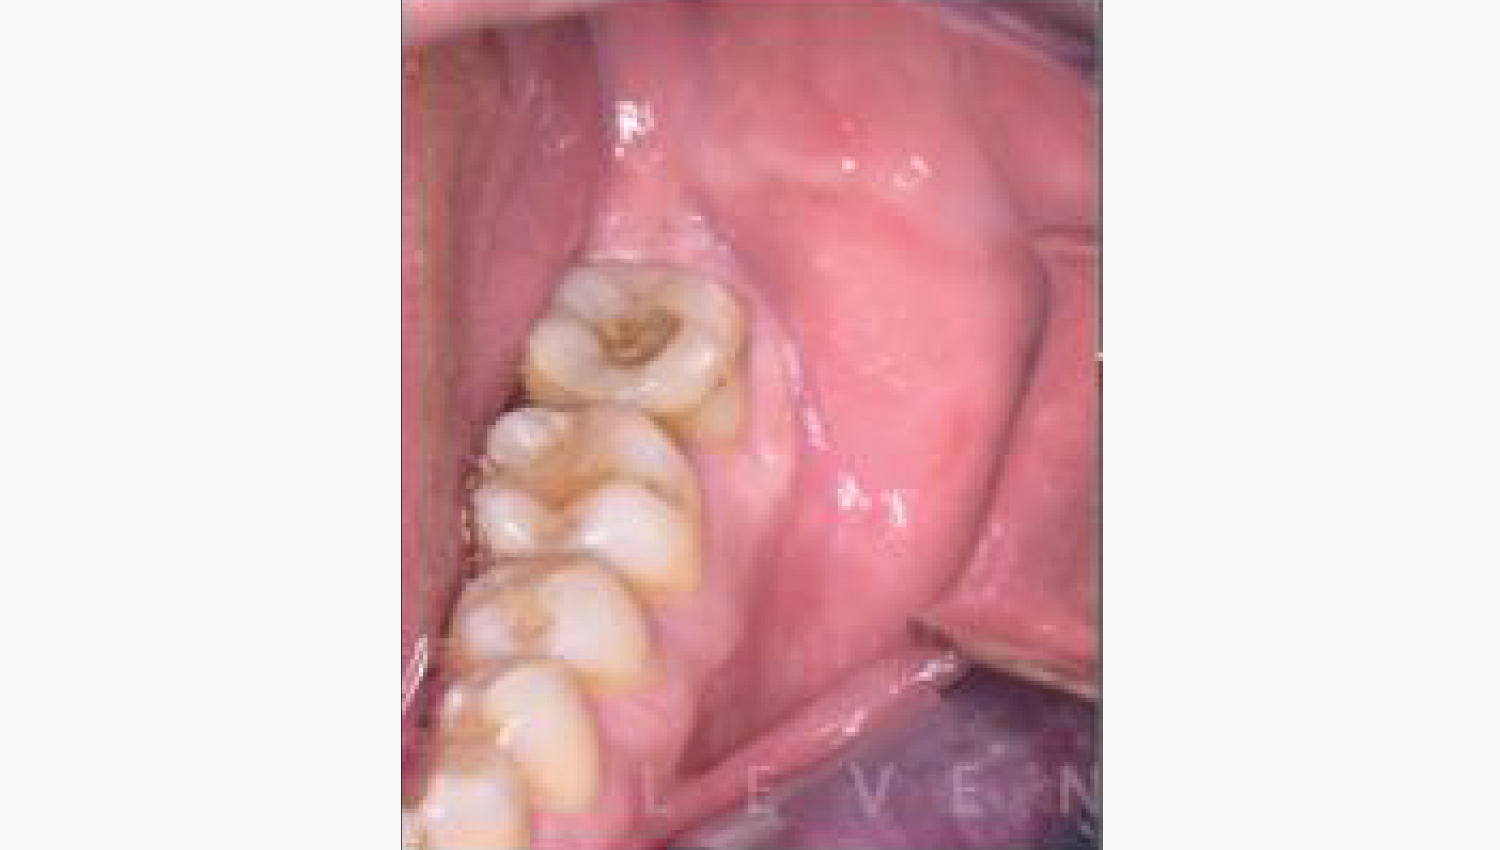

1.Initial Clinical view.